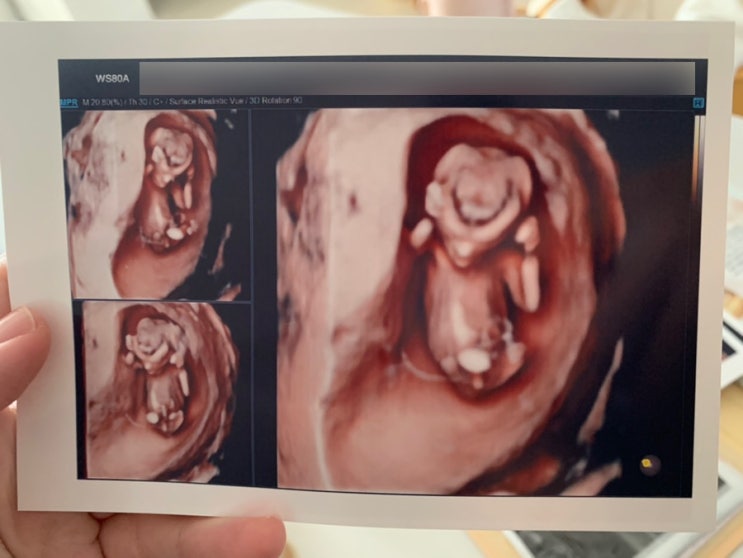

둘째가 찾아오다. 임신 12주까지의 일상

추석 일주일 전 쯤..? 뭔가 알 수 없는 직감이 파바박 하고 왔는데 마침 생리예정일도 지나있네..? 첫째때 ...